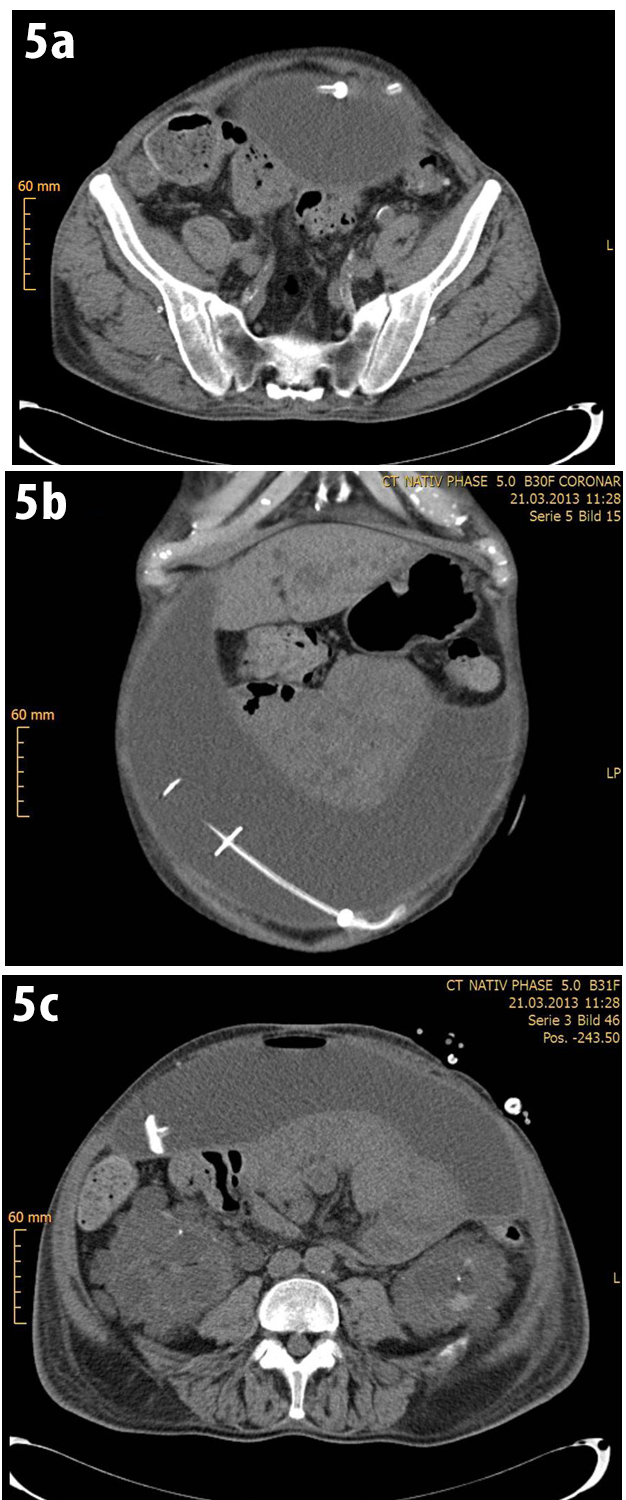

CT showed the instilled dialysate entrapped in a cyst that enclosed the inner tip of the Tenck-hoff catheter (Fig 5).

Figure 5: CT showed the instilled dialysate entrapped in a cyst that enclosed the inner tip of the Tenckhoff catheter (a-c).